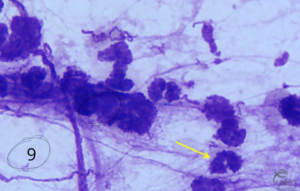

Hyphes et spores fongiques – Photo 9

Peuvent être observées, souvent fixées aux macrophages.

Fréquentes chez les chevaux :

• En écurie,

• Nourris avec foin poussiéreux/moisi,

• Même sans signes cliniques